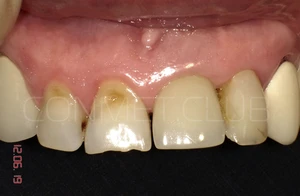

Ситуация в полости рта через 10 лет после операции. Обратите внимание на сохранность межзубных сосочков около имплантата и полное отсутствие рецессии десны на поддесневой, полированной части имплантата.

Фото этой же коронки через 15 лет после операции.